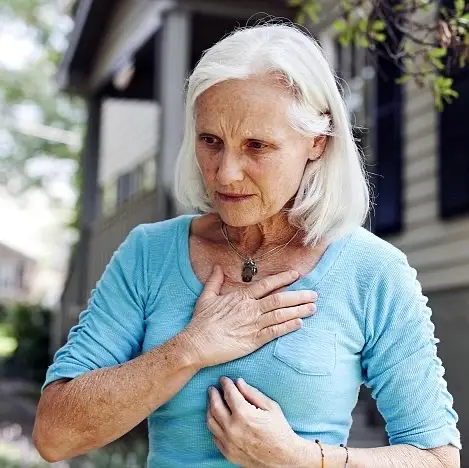

Unusual fatigue ranks as the primary early warning sign, affecting 71% of heart attack survivors surveyed.

It encompasses extreme exhaustion, diminished motivation, and overwhelming tiredness.

Everyday tasks may suddenly feel arduous due to added stress on your heart, which strains to pump blood if there’s a blockage, leaving you drained.

Besides fatigue, other early indicators may involve chest tightness or breathlessness during physical activity. Breathlessness can also result from stress.